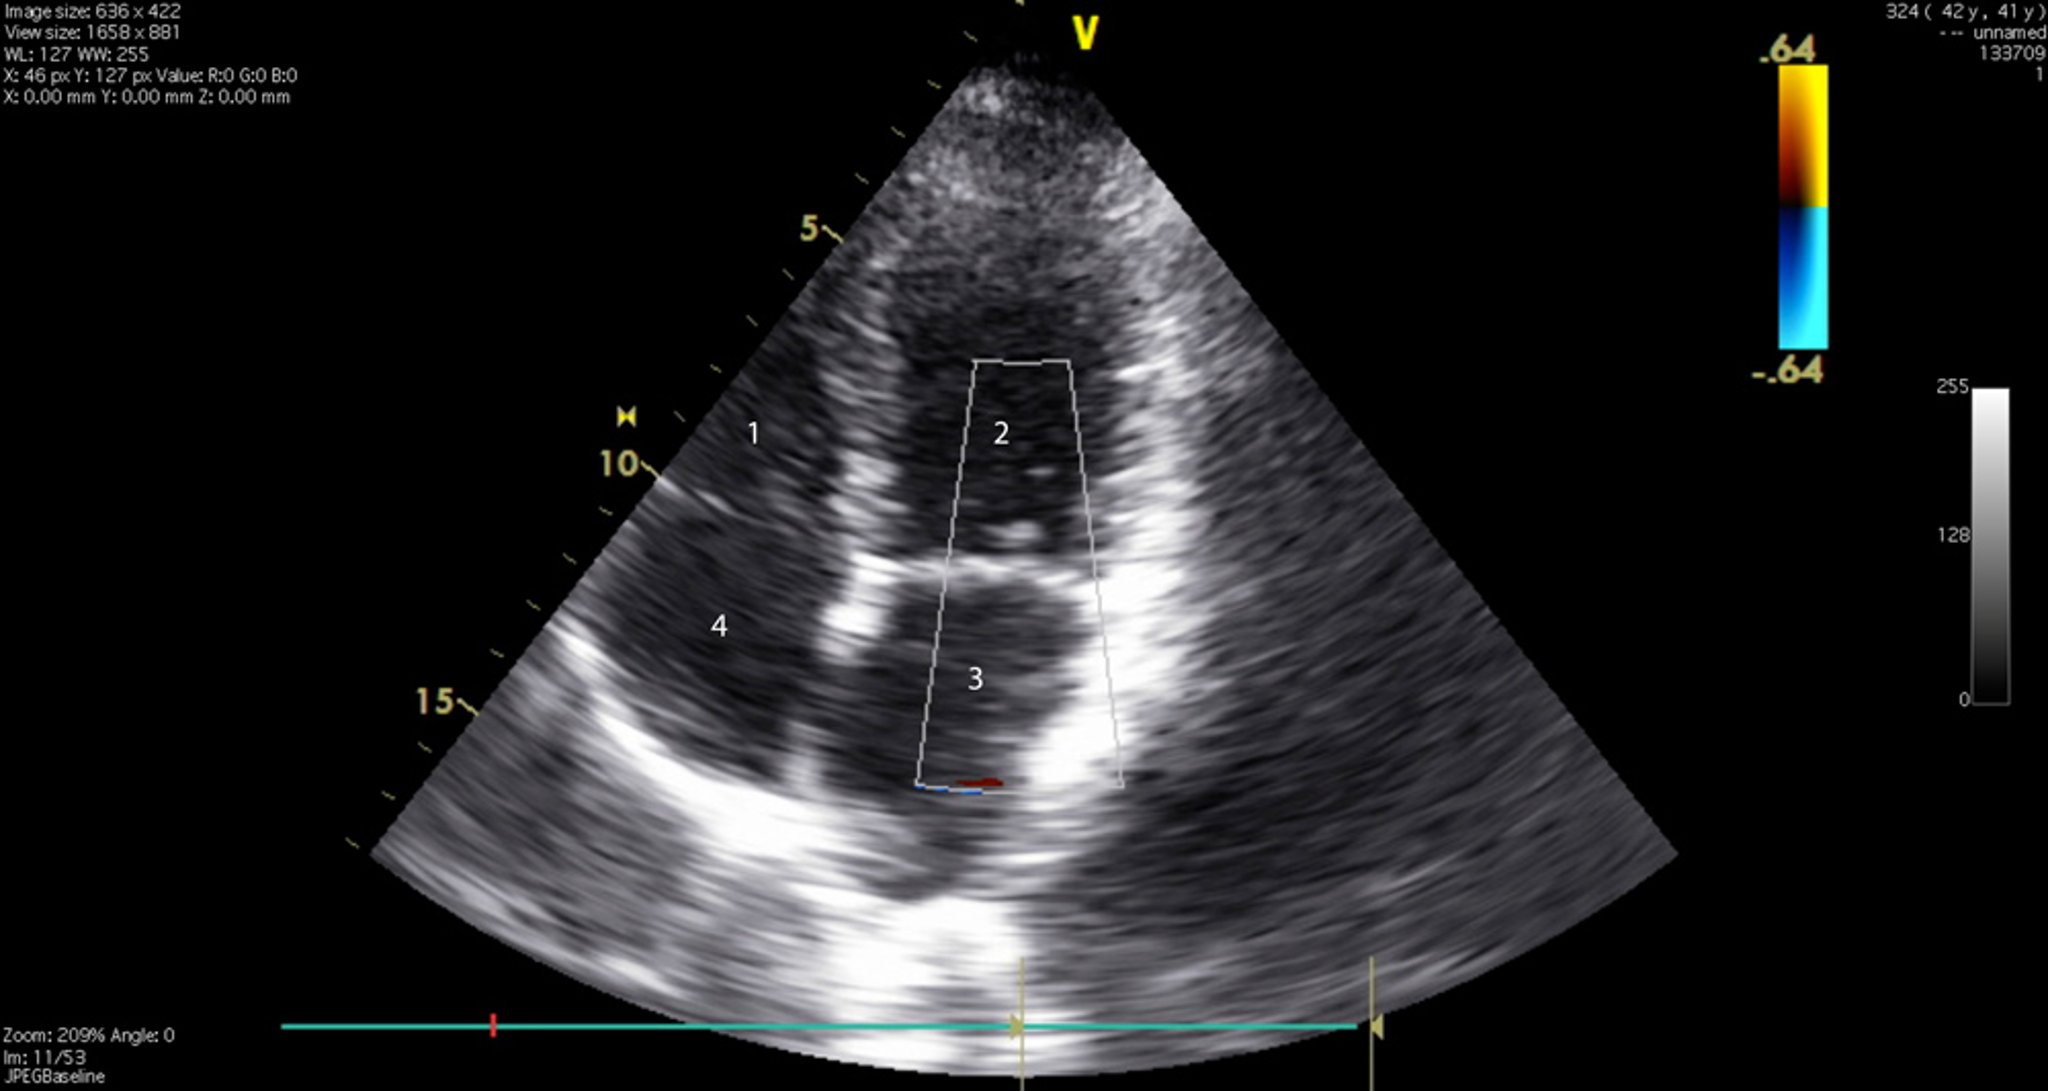

Ecocardiograma (incidência de 4 câmeras)

Essa imagem mostra as 4 câmaras cardíacas e as valvas tricúspide e mitral. 1 = ventrículo direito; 2 = ventrículo esquerdo; 3 = átrio esquerdo; 4 = átrio direito.